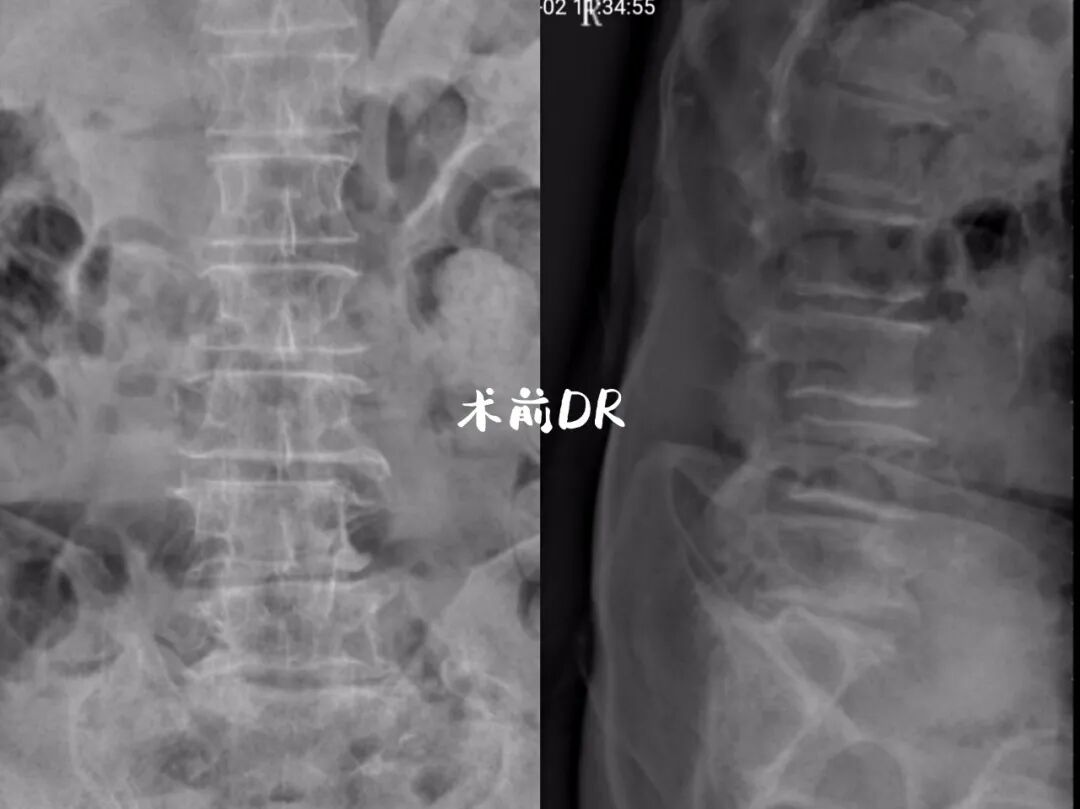

经检查发现是因腰椎滑脱伴腰椎管狭窄

引起腰痛及双下肢麻木疼痛

由于常年的腰椎压迫,需要尽快接受手术治疗,但患者的的年龄过大,并不适合传统的大面积开放治疗,患者抵抗力差并不能做到很好的恢复,面对传统的开放性手术手术风险非常大